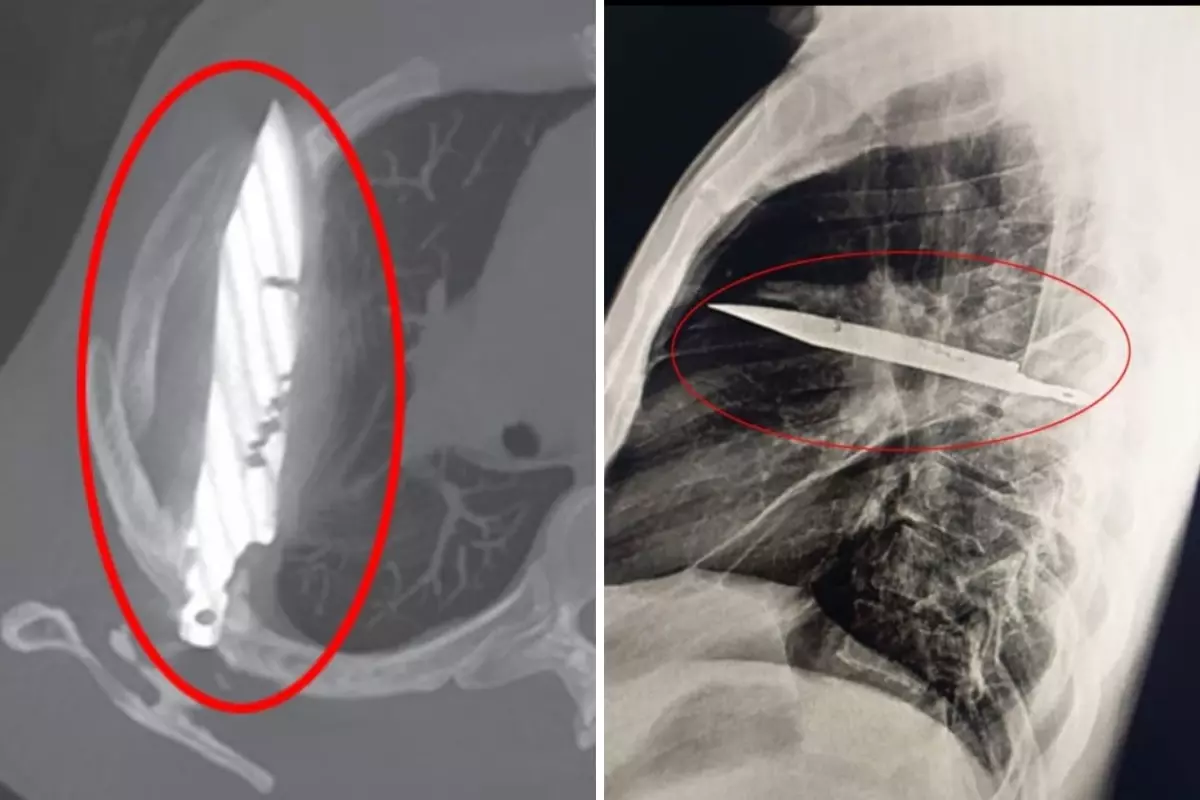

Göğüs ağrısıyla hastaneye gitti, gözlerine inanamadı: Göğsünde 8 yıldır av bıçağıyla yaşadığı ortaya çıktı!